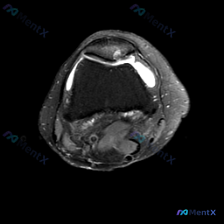

刚看到这份膝关节MRI的影像资料,整理了完整的分析思路跟大家分享一下。 一、病例影像基本信息 本次提供的是膝关节MRI T2序列轴位图像,主要显示髌股关节层面,影像观察结果如下: 1. 髌骨软骨:髌骨外侧关节面软骨信号不均匀,局部信号增高、厚度不均,软骨轮廓欠光滑;髌骨软骨下骨骨髓信号未见明显异常...

最近遇到一份挺有讨论价值的膝关节MRI读片请求,整理一下资料和分析思路分享给大家。 病例影像基础信息 这是一张膝关节MRI-T2序列的轴位图像,扫描层面在髌股关节层面,可以清晰看到前方的髌骨、后方的股骨滑车以及周围支持带软组织。 影像所见核心信息 1. 骨性结构: 髌骨形态完整,骨皮质轮廓清晰,股骨...